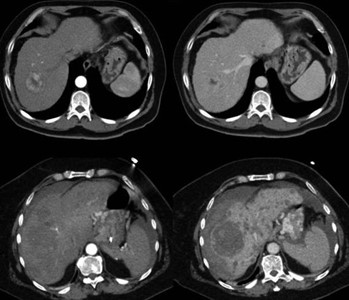

La hiperplasia nodular focal es el segundo tumor benigno más frecuente después del hemangioma. Tiene mayor incidencia en mujeres jóvenes. Histológicamente es un tumor hiperplásico que conserva los mismos componentes del tejido hepático normal, pero con una arquitectura alterada (hepatocitos normales + células de Kupffer + conductos biliares primitivos no conectados con la vía biliar normal). Presentan una cicatriz central de tejido fibroso con estructuras vasculares dilatadas y ectásicas. En la tomografía multicorte sin contraste intravenoso se evidencia como una lesión homogénea bien definida, hipo o isodensa con respecto al parénquima hepático. En la tomografía multicorte multifásica, después de la administración del medio de contraste, tiene un comportamiento típico.

- Fase arterial: reforzamiento intenso.

- Fase portal: es isodenso o ligeramente hiperdenso con respecto al parénquima.

- Fase tardía: lesión totalmente isodensa, no se visualiza, excepto porque puede producir efecto de masa sobre el parénquima adyacente.

La cicatriz central (Anexos 21 y 22), al estar menos vascularizada, no refuerza en fase arterial. Sin embargo, en fase tardía muestra hiperdensidad cuando ya el resto de la lesión se ha hecho isodensa.(18)